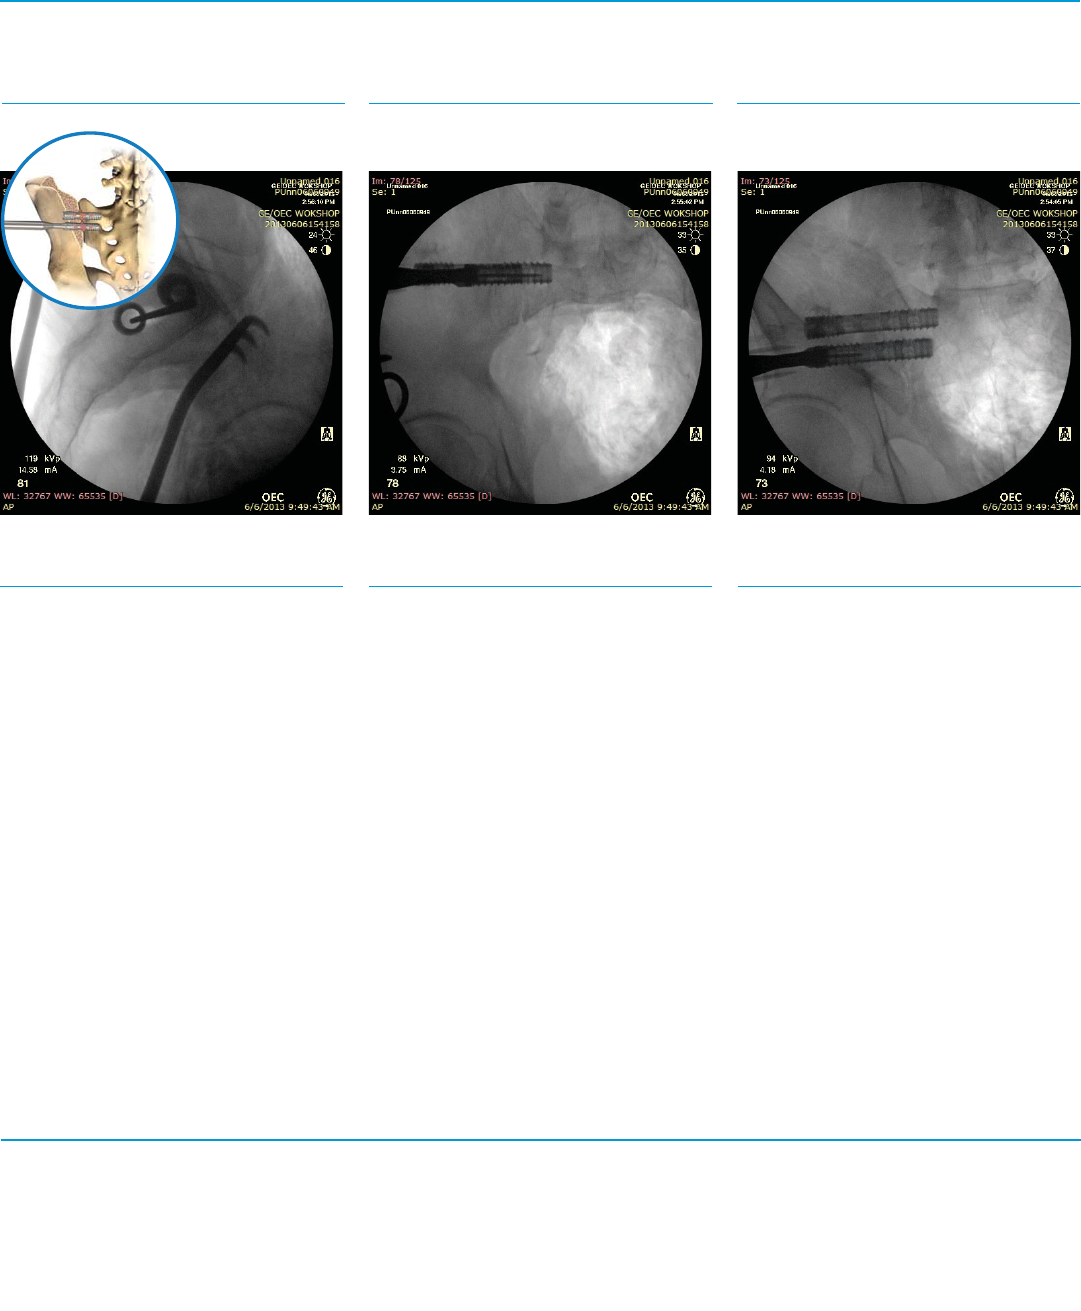

Fig. 15a SFig. 15b SFig. 15c S

Second Implant Targeting

Step 15

Repeat Step 3 for placement of the second

Trocar Steinmann Pin.

Lateral View (Fig. 15a)

Inlet View (Fig. 15b) Outlet View (Fig. 15c)